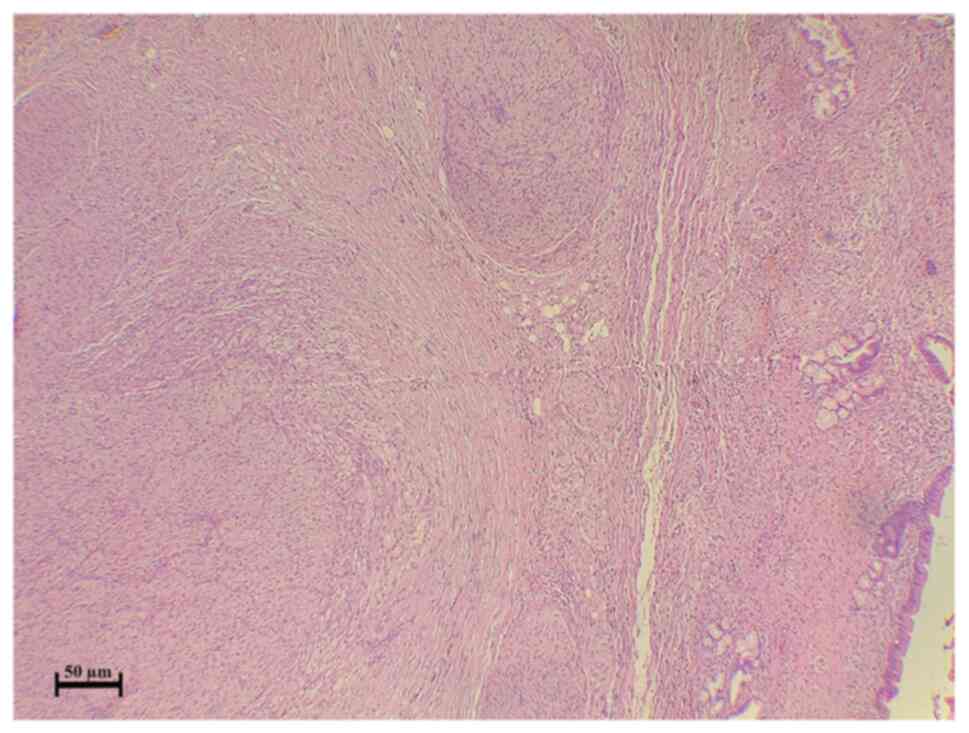

The case was discussed by the multidisciplinary team of Smart Health Tower, and by reviewing the imaging findings, the team suspected thickening in the area of the stricture; therefore, it was decided that surgery should be performed and not an ERCP. Under general anesthesia, a laparotomy was made through donor incisions. Intraoperatively, a hard bile duct mass of 2 cm in the greatest dimension was observed with multiple enlarged lymph nodes in the peri-hepatic region. It was suspected to be a case of bile duct cancer. As a result, bile duct excision with proximal and distal safe margins, as well as peri-hepatic lymphadenectomy, was performed (14 lymph nodes were resected). A Roux-en-Y jejunostomy was performed, and a drain was left in the subhepatic region. The resected specimens were sent for histopathological analysis, which revealed bile duct traumatic neuroma (Fig. 2). Immunostaining revealed diffuse and strong positivity in the disorganized nerve bundle (Fig. 3). SOX10 was used for the confirmation of the neural nature of the lesion because SOX10 shows an increased specificity for soft tissue tumors of neural crest origin (6).

Figure 2

Section illustrating a common bile duct with benign epithelial lining and benign glands with wall thickening, inflammation, fibrosis and numerous disordered nerve bundles, both intra and extramurally.